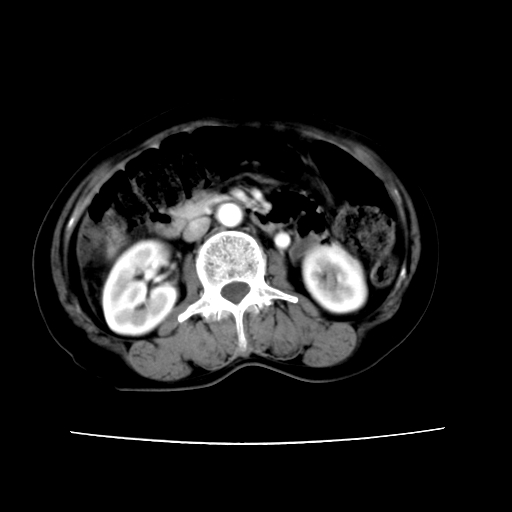

2008-11-10ct平扫(其间去中山医院诊治未行特殊治疗)

2008-11-10ct平扫见并肝内、血膜下血肿基本吸收,肝内低密度灶缩小。此时再做增强ct应有显着意义。对患者/医者都好!

从平扫+增强及治疗后复查片,病变明显缩小,不考虑肝癌出血可能,还是考虑为良性病变可能性大;单纯血肿并包膜下积液吧,病变强化没法解释,肝血管破裂出血吧,增强不符合典型血管瘤的表现,良性肿瘤破裂出血吧,复查片看来好像也不太支持(没做强化也不太好说)。本人还是考虑单纯肝内血肿并包膜下积液,强化是不是血管有外渗。

患者自6月至11月,如果是肝癌,没有经过特殊治疗,想必应该会有所进展吧,而不是ct所见,反而似有病灶减小的趋势。建议增强。